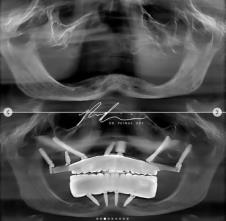

Stomatolog dr Perman Rejsi iz Sjedinjenih Američkih Država na svom Instagramu podelio je transformaciju jednog pacijenta, a fotografije pre i posle intervencije prikazuju nam jednog mladića bez zuba, sa gotovo "zgužvanim" donjim delom lica i neverovatnu promenu nakon što su mu ugrađeni implanti. Lice mu je doslovno vraćeno u prirodno i prvobitno stanje i konačno je mogao da se osmehne - sebi, životu i mnogo lepšoj budućnosti koja ga očekuje.

Dr Pej Rej, kako je poznat na mrežama, pokazao je putem fotografija i video snimaka kako funkcioniše čitava procedura, pa pomenuo koliko je implantologija značajna grana stomatologije, pogotovo kada su u pitanju ljudi koji su izgubili sve zube - a samim tim i nadu i volju za životom - koje im on, svojim umećem i znanjem, vraća.

Inače, dr Pejman Rejsi je ugledni stomatolog specijalizovan za oralnu implantologiju i rekonstrukcije celih zubnih lukova i usne duplje. Doktorat je stekao na Stomatološkom fakultetu Univerziteta u Tenesiju i nosilac je prestižne titule Diplomate Američkog odbora za oralnu implantologiju (DABOI), prenosi Blic žena.